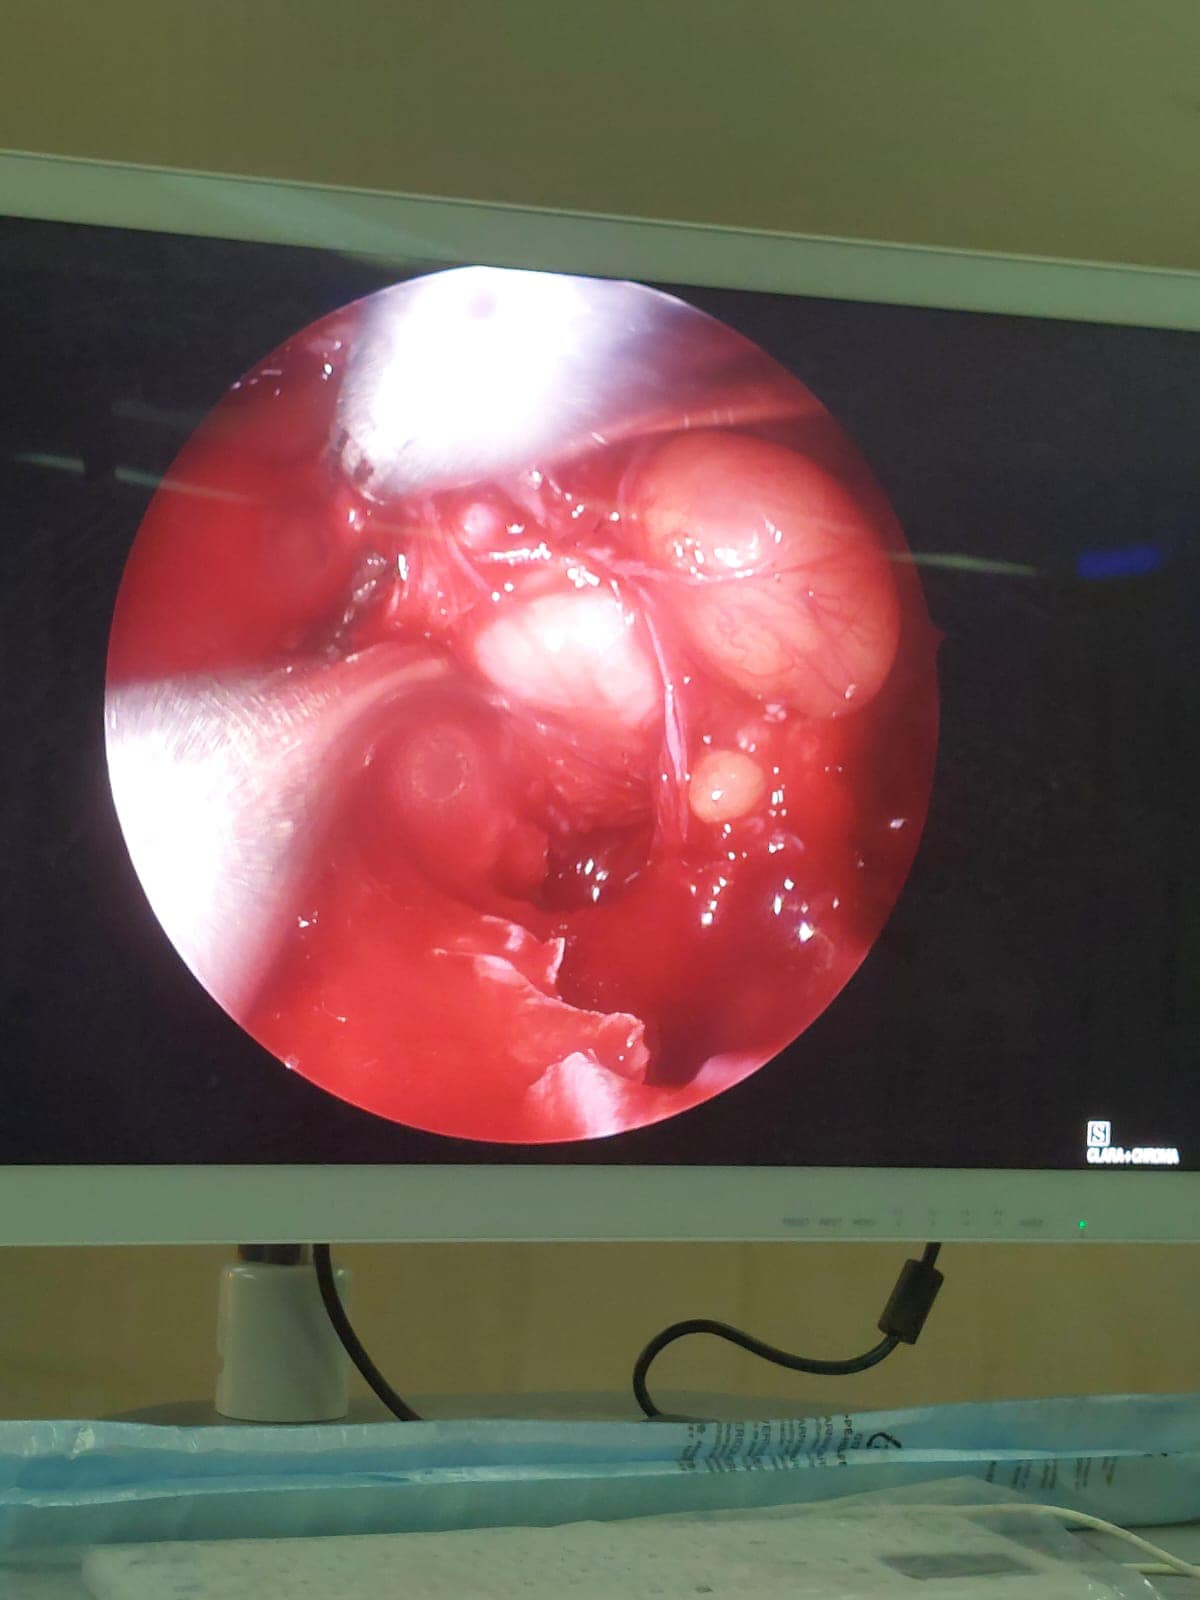

الجامعي من استئصال ورم دموي (انجيوفيبروما) بالأنف ممتد إلى الجيب الأنفي الوتدي و ملتصق بالشريان السباتي وممتد إلى المخ، لشاب في مقتبل العمر ١٦ سنة يدعي “ج. ع. ف” بمركز المنشاه، وذلك في عملية استغرقت ٥ ساعات متواصلة.

وقال الدكتور سمير عبدالمجيد مدير مستشفي الطوارئ بالحرم الجامعي الجديد، أن المريض وصل الي المستشفي بحالة انسداد الأنف وتاريخ مرضي لنوبات نزيف شديدة ومتكررة من الأنف كادت تودي بحياته، فعلي الفور تم إنهاء إجراءات دخول المريض بالقسم، وعمل الفحوصات المخبرية وشملت إجراء تحاليل دم وفصيلة دم وتجهيز ٣ أكياس دم ، وأشعة مقطعية ورنين بالصبغة، وأشعه مقطعية على الأنف والجيوب الأنفية بالصبغة، ورنين على المخ وقاع الجمجمة بالصبغة، وعقب الإنتهاء من التجهيزات اللازمة تم دخوله غرفة العمليات وخرج في حالة مستقرة.

ومن جانبه أضاف الدكتور محمد عبدالقادر سلطان رئيس قسم الأنف والأذن والحنجرة، أنه علي الفور تم تشكيل فريق طبي علي درحة عالية من المهارة نظراً لخطورة العملية ودقتها، فتم حقن الشرايين المغذية للورم الدموي قبل العملية لتقليل النزيف اثناء العملية بالأشعة التدخلية، وعقب العملية خرج المريض في حالة صحية مستقرة.